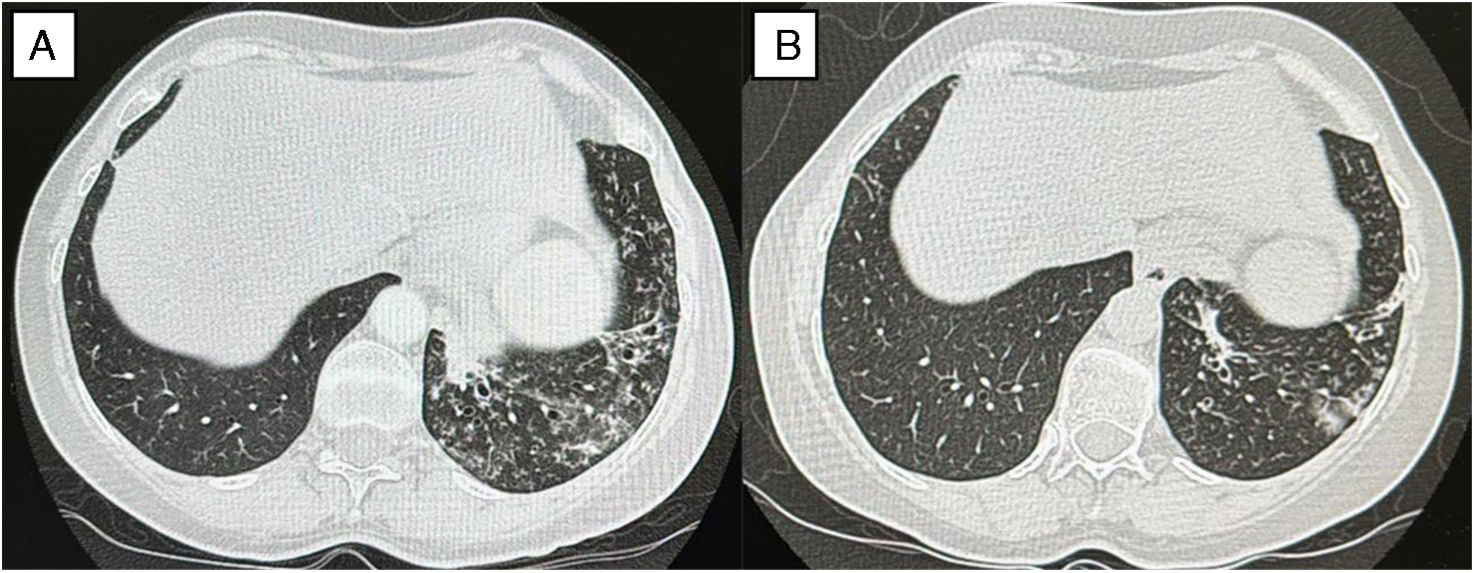

In 2024, after three bronchiectasis exacerbations requiring empirical antibiotics, sputum and bronchoscopy cultures revealed A. xylosoxidans. Two courses of trimethoprim–sulfamethoxazole failed to eradicate the microorganism, and CT imaging revealed progressive cylindrical bronchiectasis with worsening “tree-in-bud” opacities and a Bronchiectasis Severity Index (BSI) score of 7 (Fig. 1A). Nebulized levofloxacin (240mg twice daily, on–off 28-day cycles) was initiated for CBI caused by A. xylosoxidans, in addition to patient's existing maintenance therapy, leading to: marked reduction in daily sputum, resolution of exacerbations, improved lung function and CT findings (Fig. 1B), and sustained microbiological clearance over six months.

(A) Baseline CT scan demonstrating bilateral bronchiectasis in the middle lobe and lingula, accompanied by “tree-in-bud” pattern and endoluminal secretions, with associated volume loss. (B) Follow-up CT after six months of nebulized levofloxacin showing improvement and decreased “tree-in-bud” opacities.